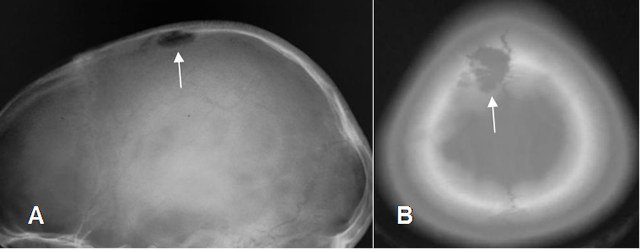

Fig 129. Granuloma eosinófilo.

A: Rx lateral y B: TAC axial. Lesión radiolúcida y de bordes definidos, pero no escleróticos, por granuloma eosinófilo.

Fig 130. Granuloma eosinófilo.

A: Rx AP de cráneo y B: RM coronal en T2. Lesión radiolúcida parietal derecha, hiperintensa en la RM, por granuloma eosinófilo.